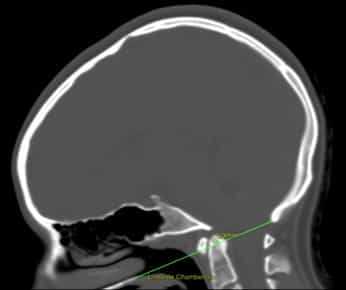

Рисунок 1. Базиллярная импрессия. КТ головного мозга с линией Чемберлена, которая соединяет заднюю стенку большого затылочного отверстия с передней стенкой твердого нёба и должна проходить по верхней части атланта. В данном случае атлант превышает границу на 5,3 мм.

Диагноз ставится при помощи измерения линии Чемберлена и/или других показателей (см. Рис.1).